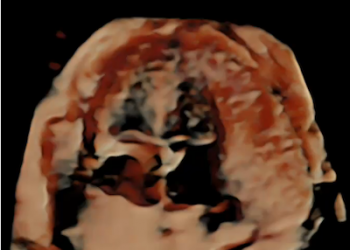

Cari colleghi, vi presentiamo la guida al counseling di Luglio 2024 sul corpo luteo emorragico. Potrete scaricarla cliccando sul link....